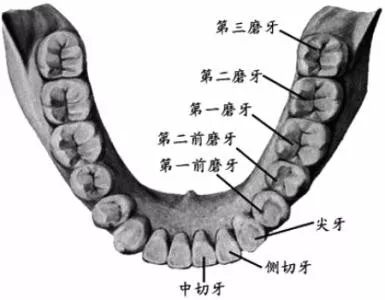

智齿,学名三大臼(jiù)齿,又叫做第三磨牙。

虽然叫做智齿,但其实和智商毫无关系...只是一般在 18 岁后长出来,正处于人类智力发育的鼎盛期而得名(小时候看郑渊洁的《智齿》,一直对自己没有长智齿而耿耿于怀,现在,悔之晚矣...)。

人类在进化过程中,进食的食物是越来越精细,颌骨(就是你的下巴)越来越短,但牙齿不会减少,有的牙齿就没有空间长出来。严肃的推断出「智齿长不好,说明你脸小」(强行安慰一波长阻生智齿的人)...